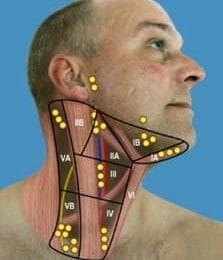

Lymfeklier ziekte

Opgezette lymfeklieren, of lymfeknopen, vormen doorgaan...

Lees Meer +